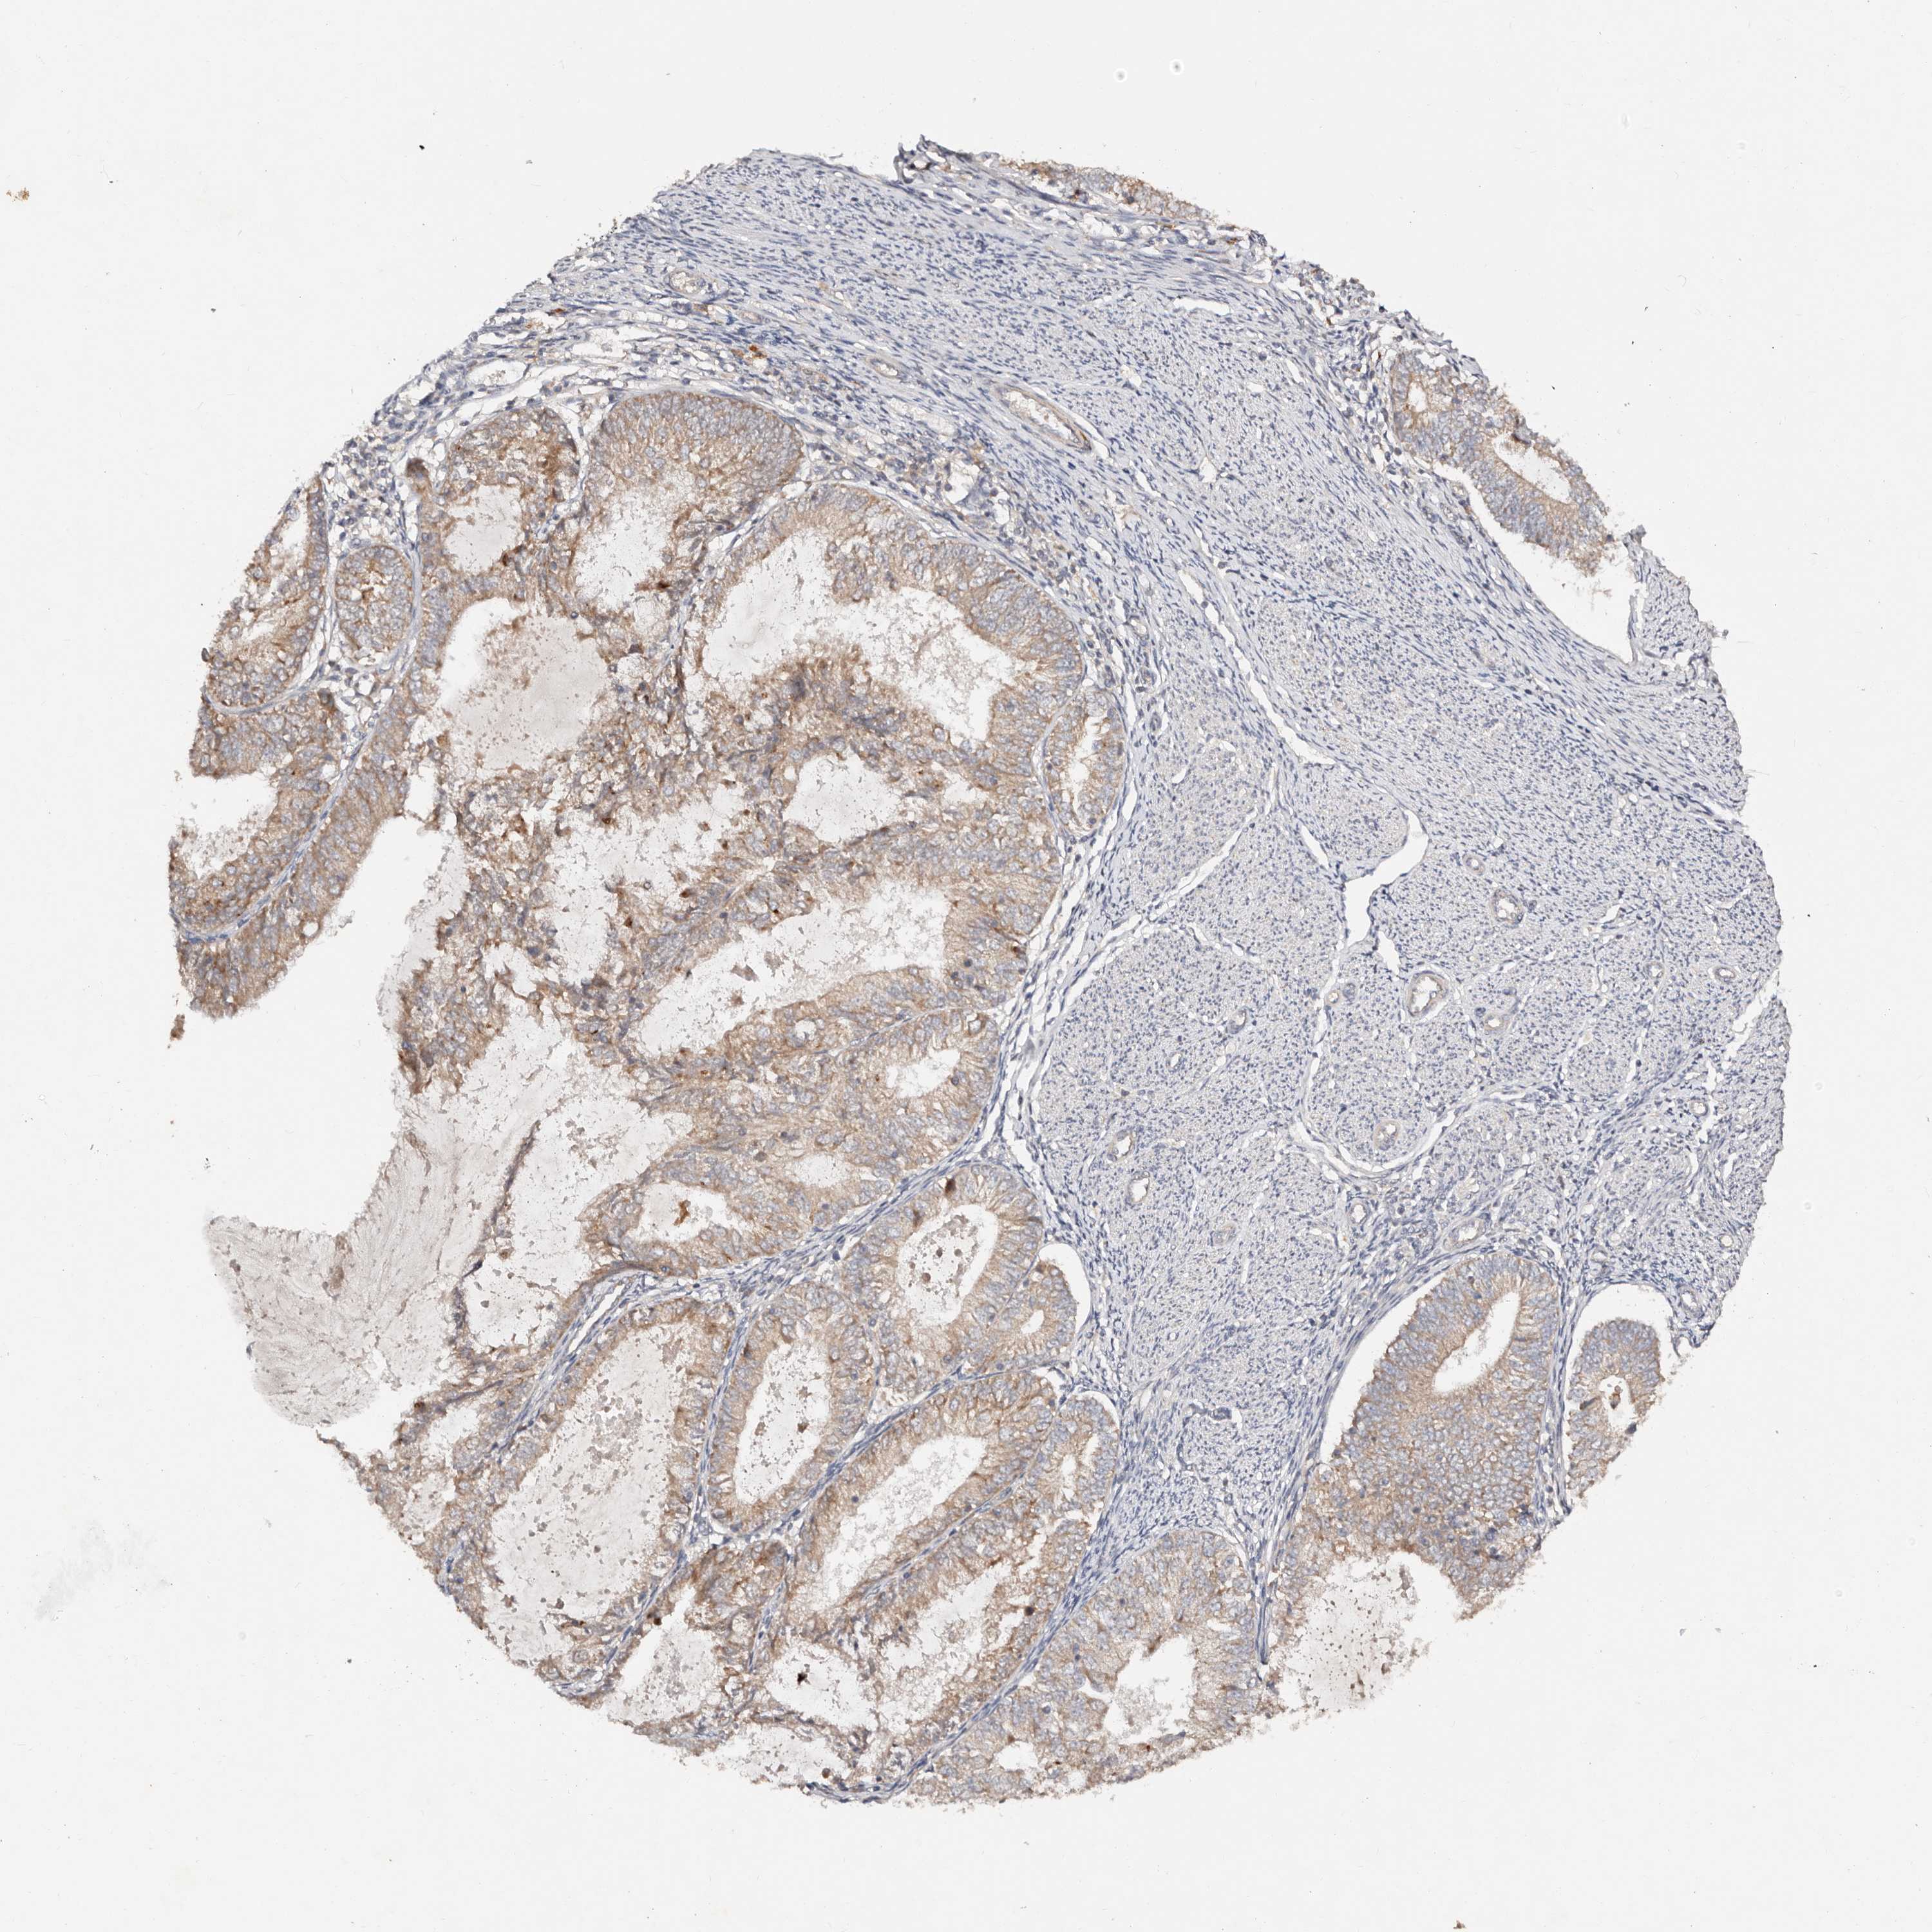

ENDOMETRIAL CANCER - Protein expressioni

A mouse-over function shows sample information and annotation data. Click on an image to view it in a full screen mode. Samples can be filtered based on level of antibody staining by selecting one or several of the following categories: high, medium, low and not detected. The assay and annotation is described here.

Note that samples used for immunohistochemistry by the Human Protein Atlas do not correspond to samples in the TCGA dataset.

Antibody stainingi

Antibody staining in the annotated cell types in the current human tissue is reported as not detected, low, medium, or high, based on conventional immunohistochemistry profiling in selected tissues. This score is based on the combination of the staining intensity and fraction of stained cells.

Each image is clickable and will lead to virtual microscopy that enables deeper exploration of all samples and also displays staining intensity scores, fraction scores and subcellular localization as well as patient and tissue information for each sample.

Antibody HPA029467

Staining

High

Medium

Low

Not detected

Intensity

Strong

Moderate

Weak

Negative

Quantity

>75%

75%-25%

<25%

None

Location

Nuclear

Cytoplasmic/membranous

Cytoplasmic/membranous,nuclear

Adenocarcinoma, NOS

Adenocarcinoma, metastatic, NOS